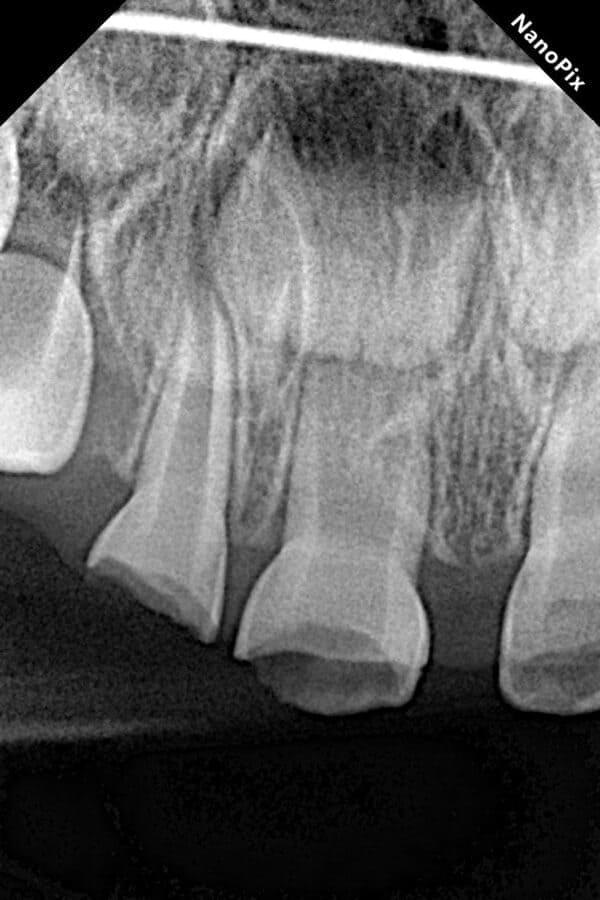

Дівчинка, 5 років. Лікування зворотнього пульпіту тимчасових зубів 85,84 та їх відновлення за допомогою стандартних металевих коронок. Лікування проводилось в умовах закису азоту кисневої седації. Період зміни зубів - 10-12 років.